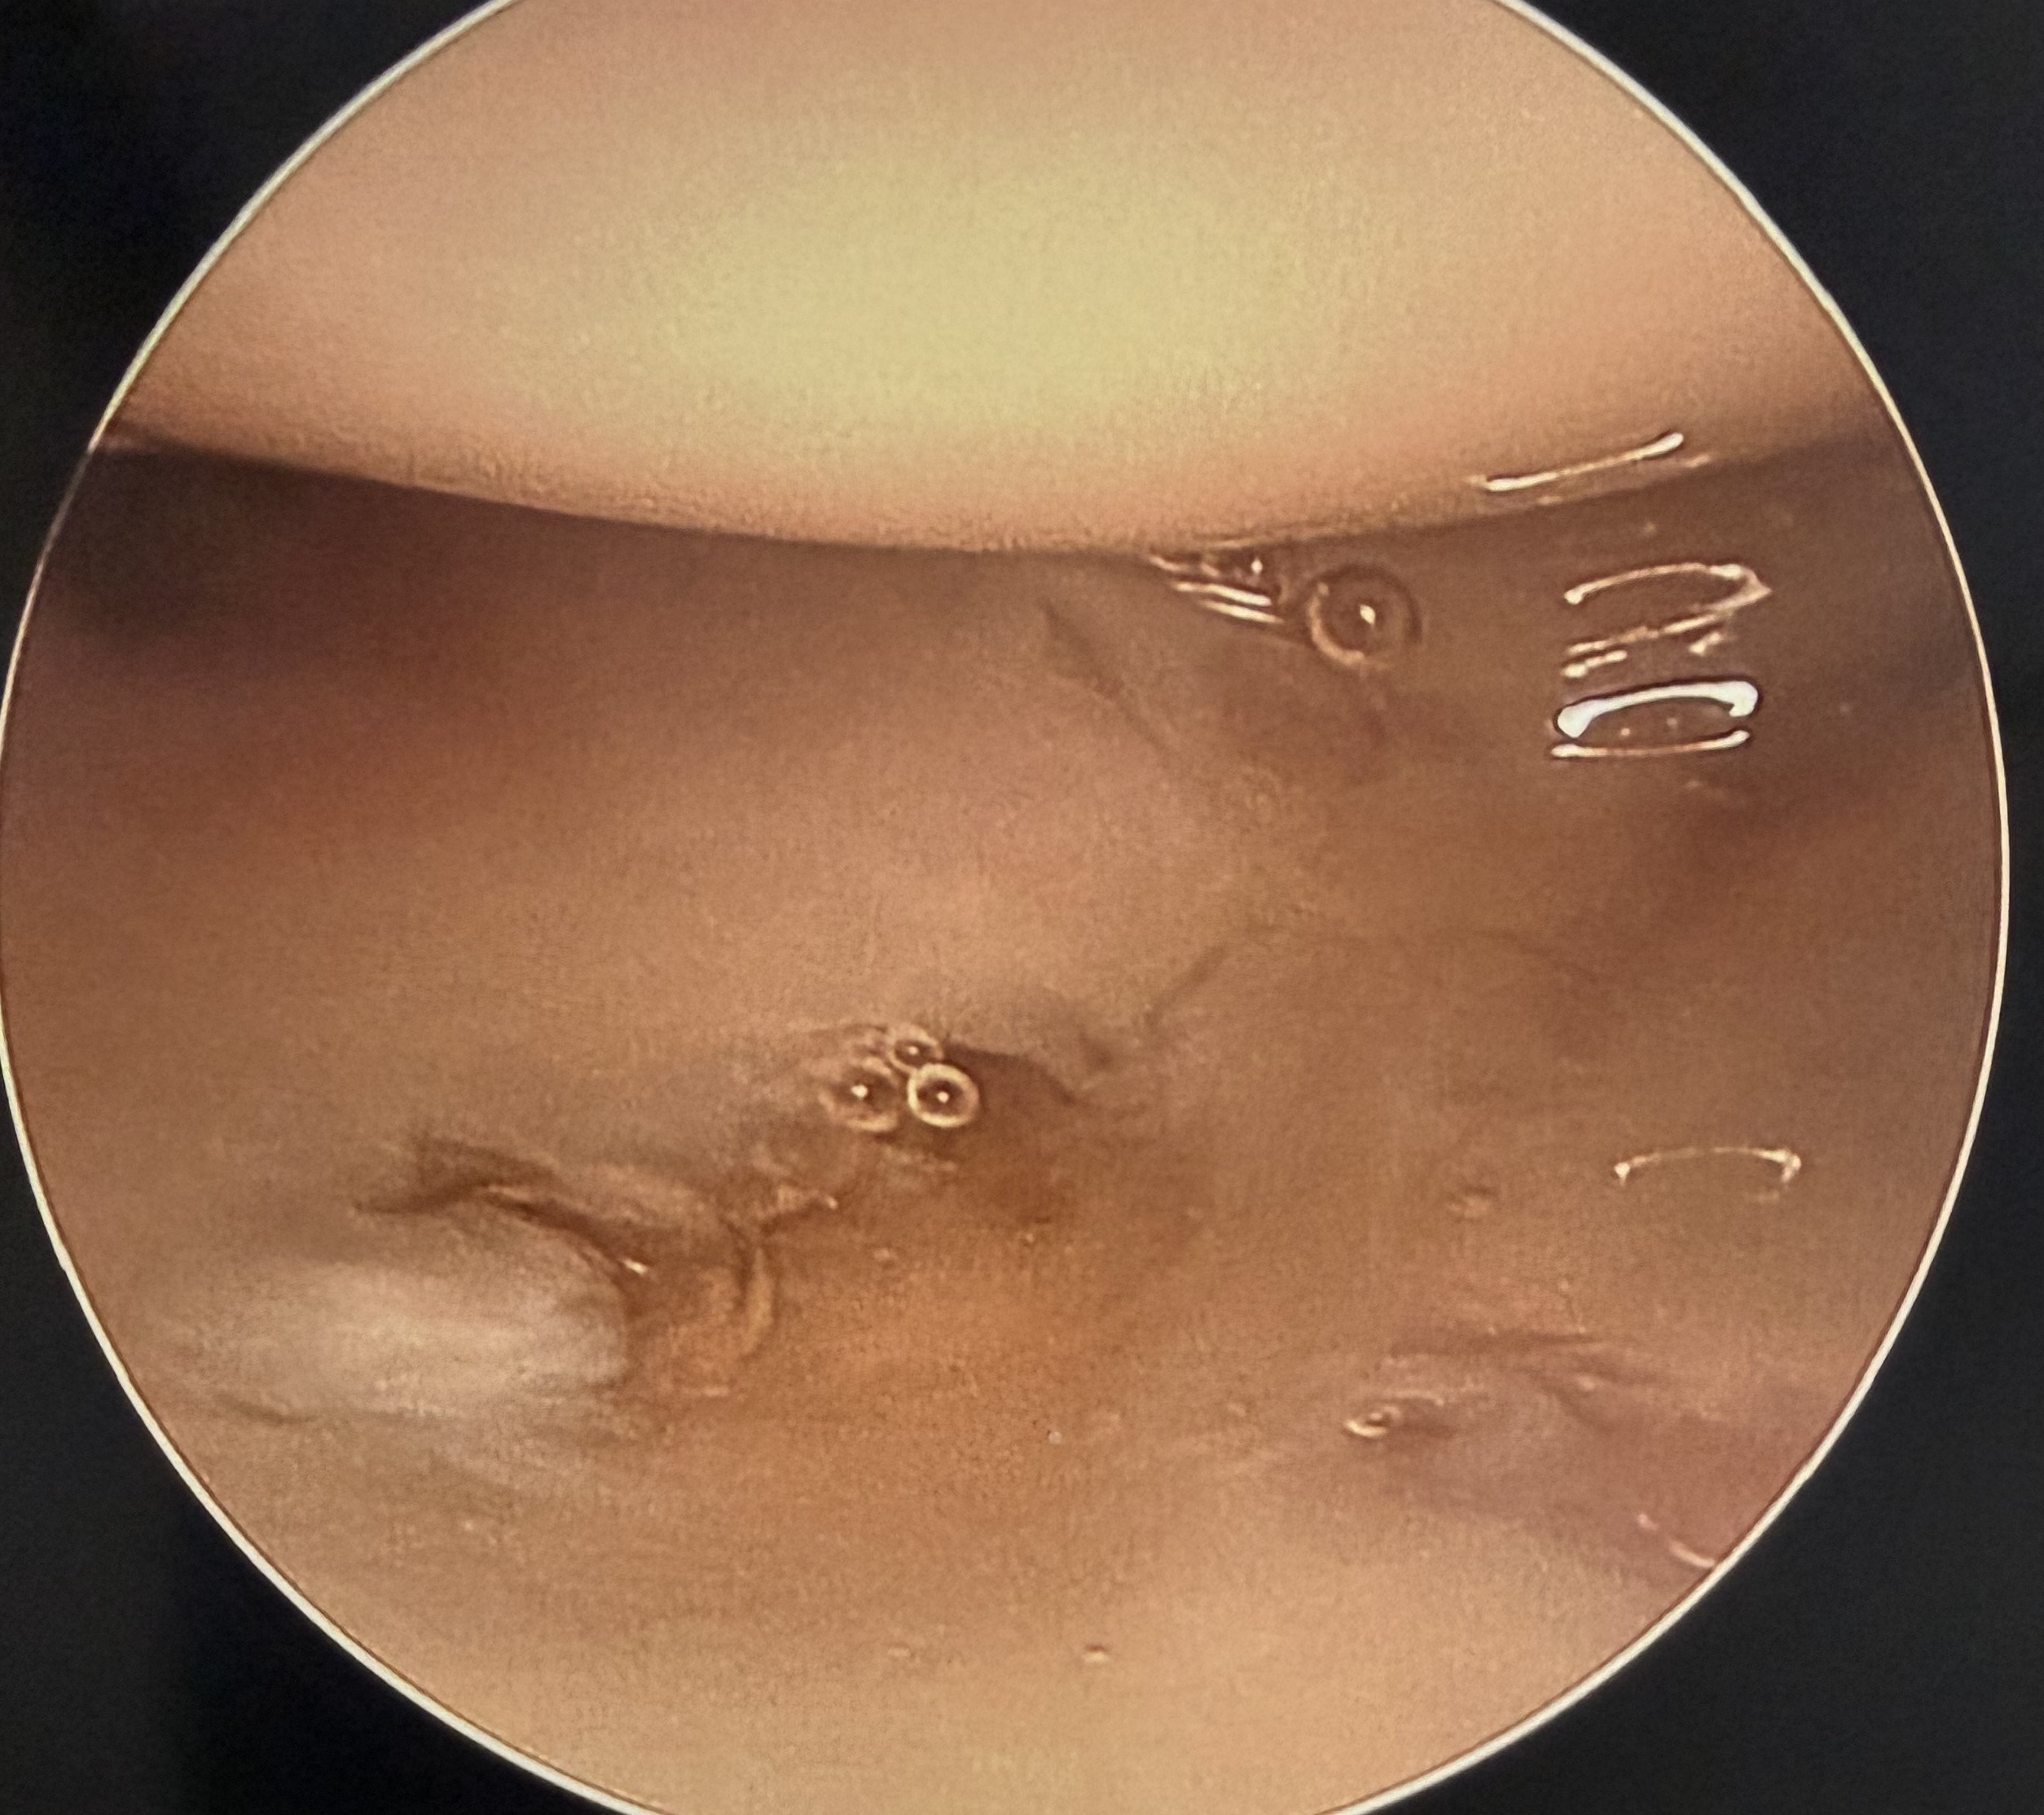

Arthroscopic wafer distal ulna resection

Technique

Wrist arthroscopy

- debride central TFCC to expose ulna head

- preserve dorsal and volar radioulnar ligaments and TFCC ulna insertion

- resect ulna cartilage and 2 mm of bone